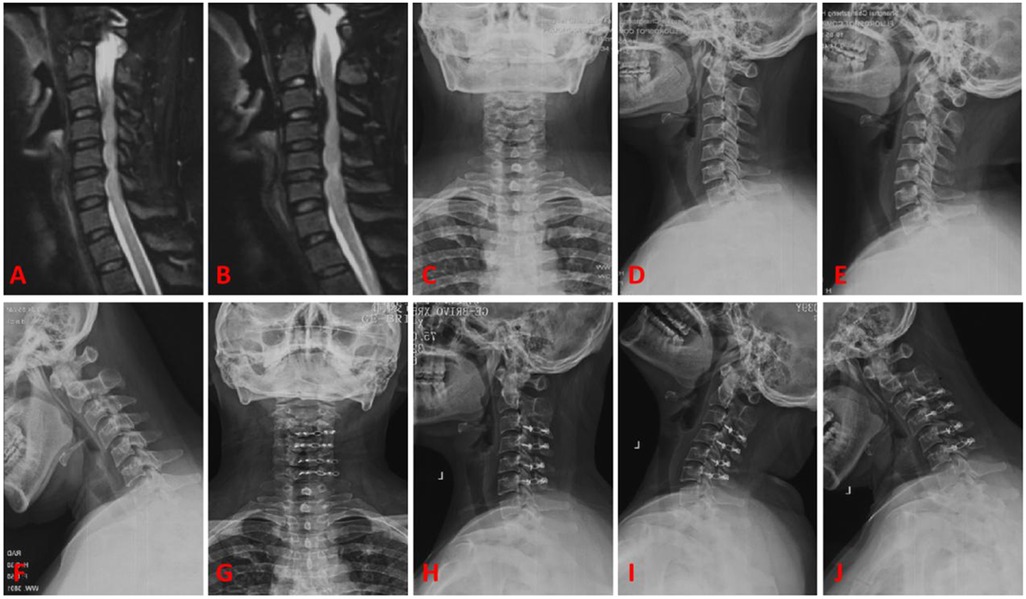

Preoperative and postoperative cervical spine lateral, flexion-extension, CT, and MRI images are obtained. The PACS 3.0 system software is used to measure the following sagittal parameters on cervical x-ray images: C0-2 Cobb angle, C2-7 sagittal vertical axis (SVA) in millimeters, C2-7 Cobb angle, T1-Slope, range of motion (ROM) of the cervical spine, displacement of the C2 vertebral body (measured as the distance between the posterior edge of the C2 vertebral body and the posterior edge of the C3 vertebral body on flexion-extension x-ray images in millimeters), and the angle of motion at the C2/3 level (measured as the difference in angle at the C2/3 level on flexion-extension x-ray images). Two physicians independently measure the imaging parameters twice using the described method. The average value of the measurements is taken as the final measurement data. The assessors are blinded to the study content. Please refer to Figure 1 for specific measurement methods.

Figure 1

X-ray images labeled A to J show lateral views of the cervical spine with varying alignments of yellow lines indicating different angles and points of measurement. Each image highlights different anatomical regions or angles, assisting in assessing spinal alignment and curvature.

Figure 1. (A) Represents C2-7 SVA (red line); (B) represents C2-7 cobb angle (red line); (C) represents C0-2 cobb angle (red line); (D) represents T1-slope (red line); (E,F) represent the difference in angle (red line) for the motion angle of C2/3 gap; (G,H) represent the difference (red line) for the displacement of C2 vertebral body; (I,J) represent the difference (red line) for ROM.